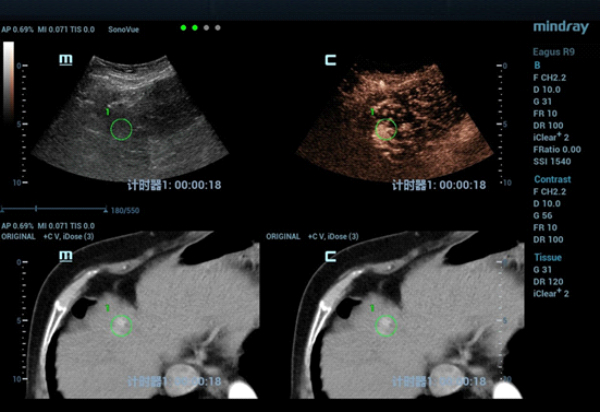

fusion-imaging-fig6

형태 5. 실시간으로 가스 범위를 모니터링 항 수 있는 융합 영상 항법 모드에 의해 수행되는 마이크로파 절제(MWA).

fusion-imaging-fig7

Figure 6. At 3 minutes of microwave ablation at 60W, the lesion was completely covered by strong echoes

형태 7. 60W에서 극초단파 절제술을 3분간 실시했을 때, 고강도 에코에 의해 종괴가 가려짐.